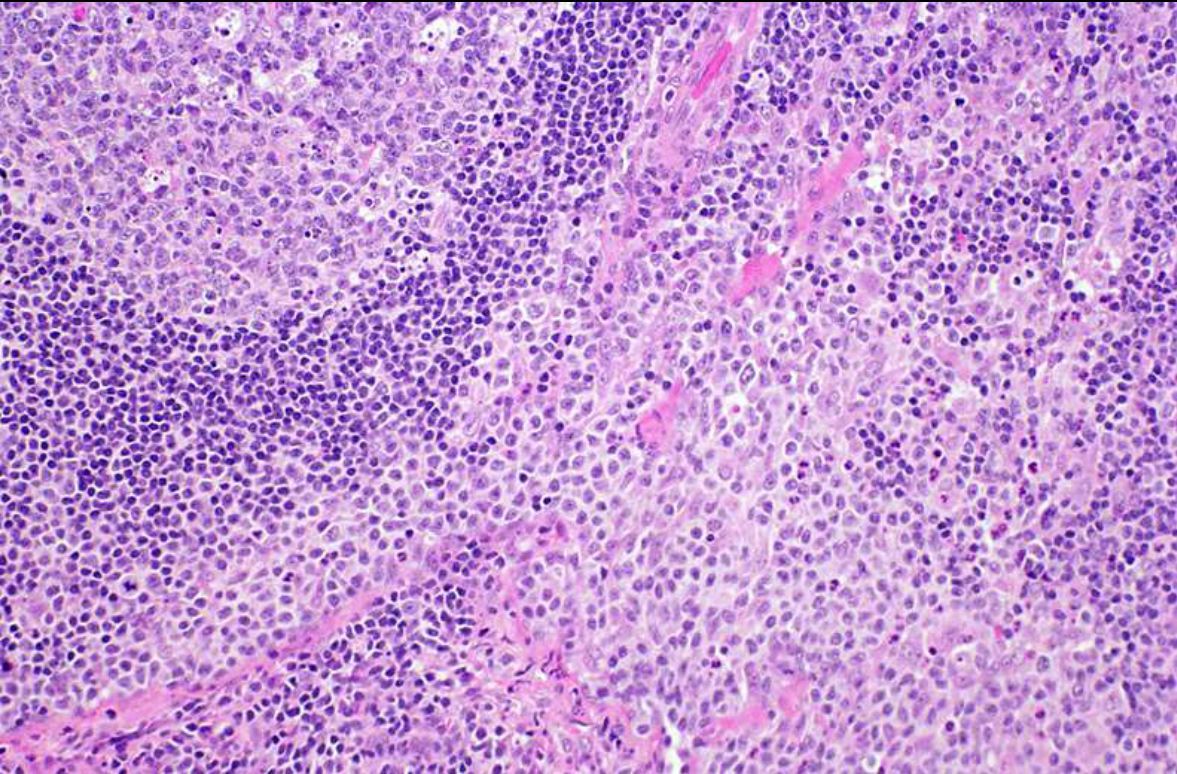

What is this lymph node lesion?

Kikuchi necrosis and debris, no neutrophils